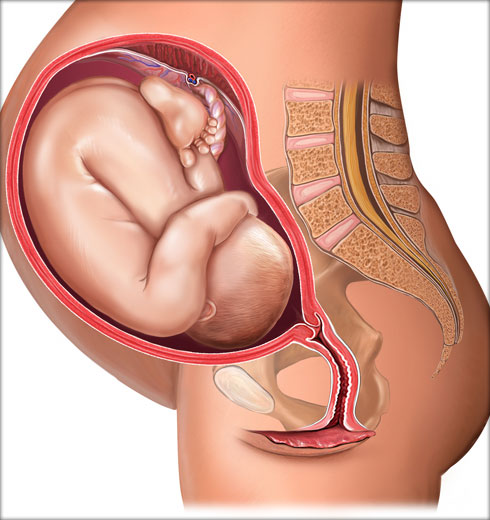

Развој бебе у стомаку мајке

од зачећа 38 недеља